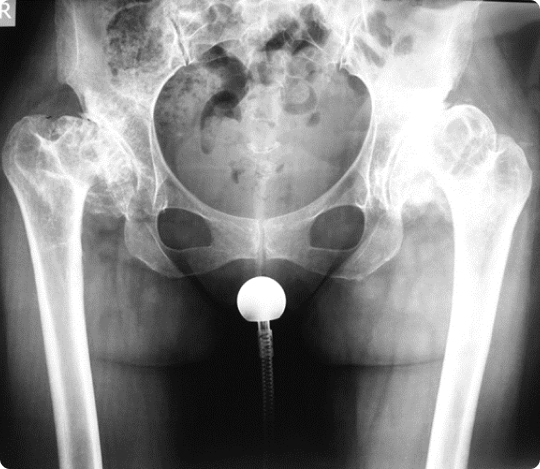

In patients with unreduced or incongruous hips and inadequate femoral head coverage, salvage pelvic osteotomies, such as the Chiari or the Shelf osteotmy, have been somewhat successfully performed in order to delay the development of end-stage arthtrits. When, however, the latter has set, the treatment of choice remains total hip arthroplasty, which can reliably alleviate the patients’ pain and improve functional outcomes, although arthroplasty for dysplasia has been associated with an increased complication profile compared to arthropasty for primary hip osteoarthritis. Finally, hip resurfacing, a more bone – preserving type of hip arthroplasty, has been described in dysplastic hips as well, but given the frequency of proximal femoral deformities in such patients it must be implemented after strict patient selection, so as to avoid unacceptable complication rates.